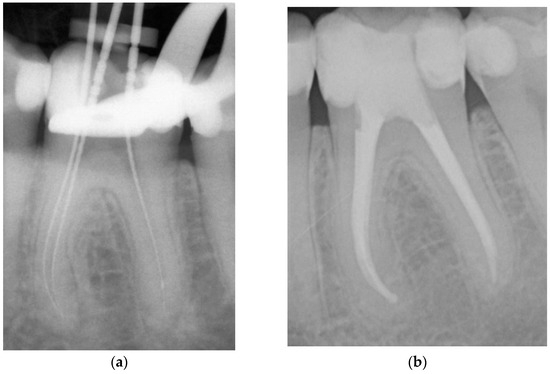

Figure 2. Representative example of root canal filling using the single-cone obturation technique with gutta-percha and AH Plus® (SCGP); working length radiograph of tooth 26 (a); 7-year follow-up radiograph showing complete apical healing (b). - Matching-taper single-cone obturation with gutta-percha and the silicon-based sealer GuttaFlow® (SCGF) (Figure 3).

Figure 3. Representative root canal filling using the single-cone obturation technique with gutta-percha and GuttaFlow® (SCGF); working length radiograph of tooth 46 (a); 6-year follow-up radiograph showing complete apical healing (b).